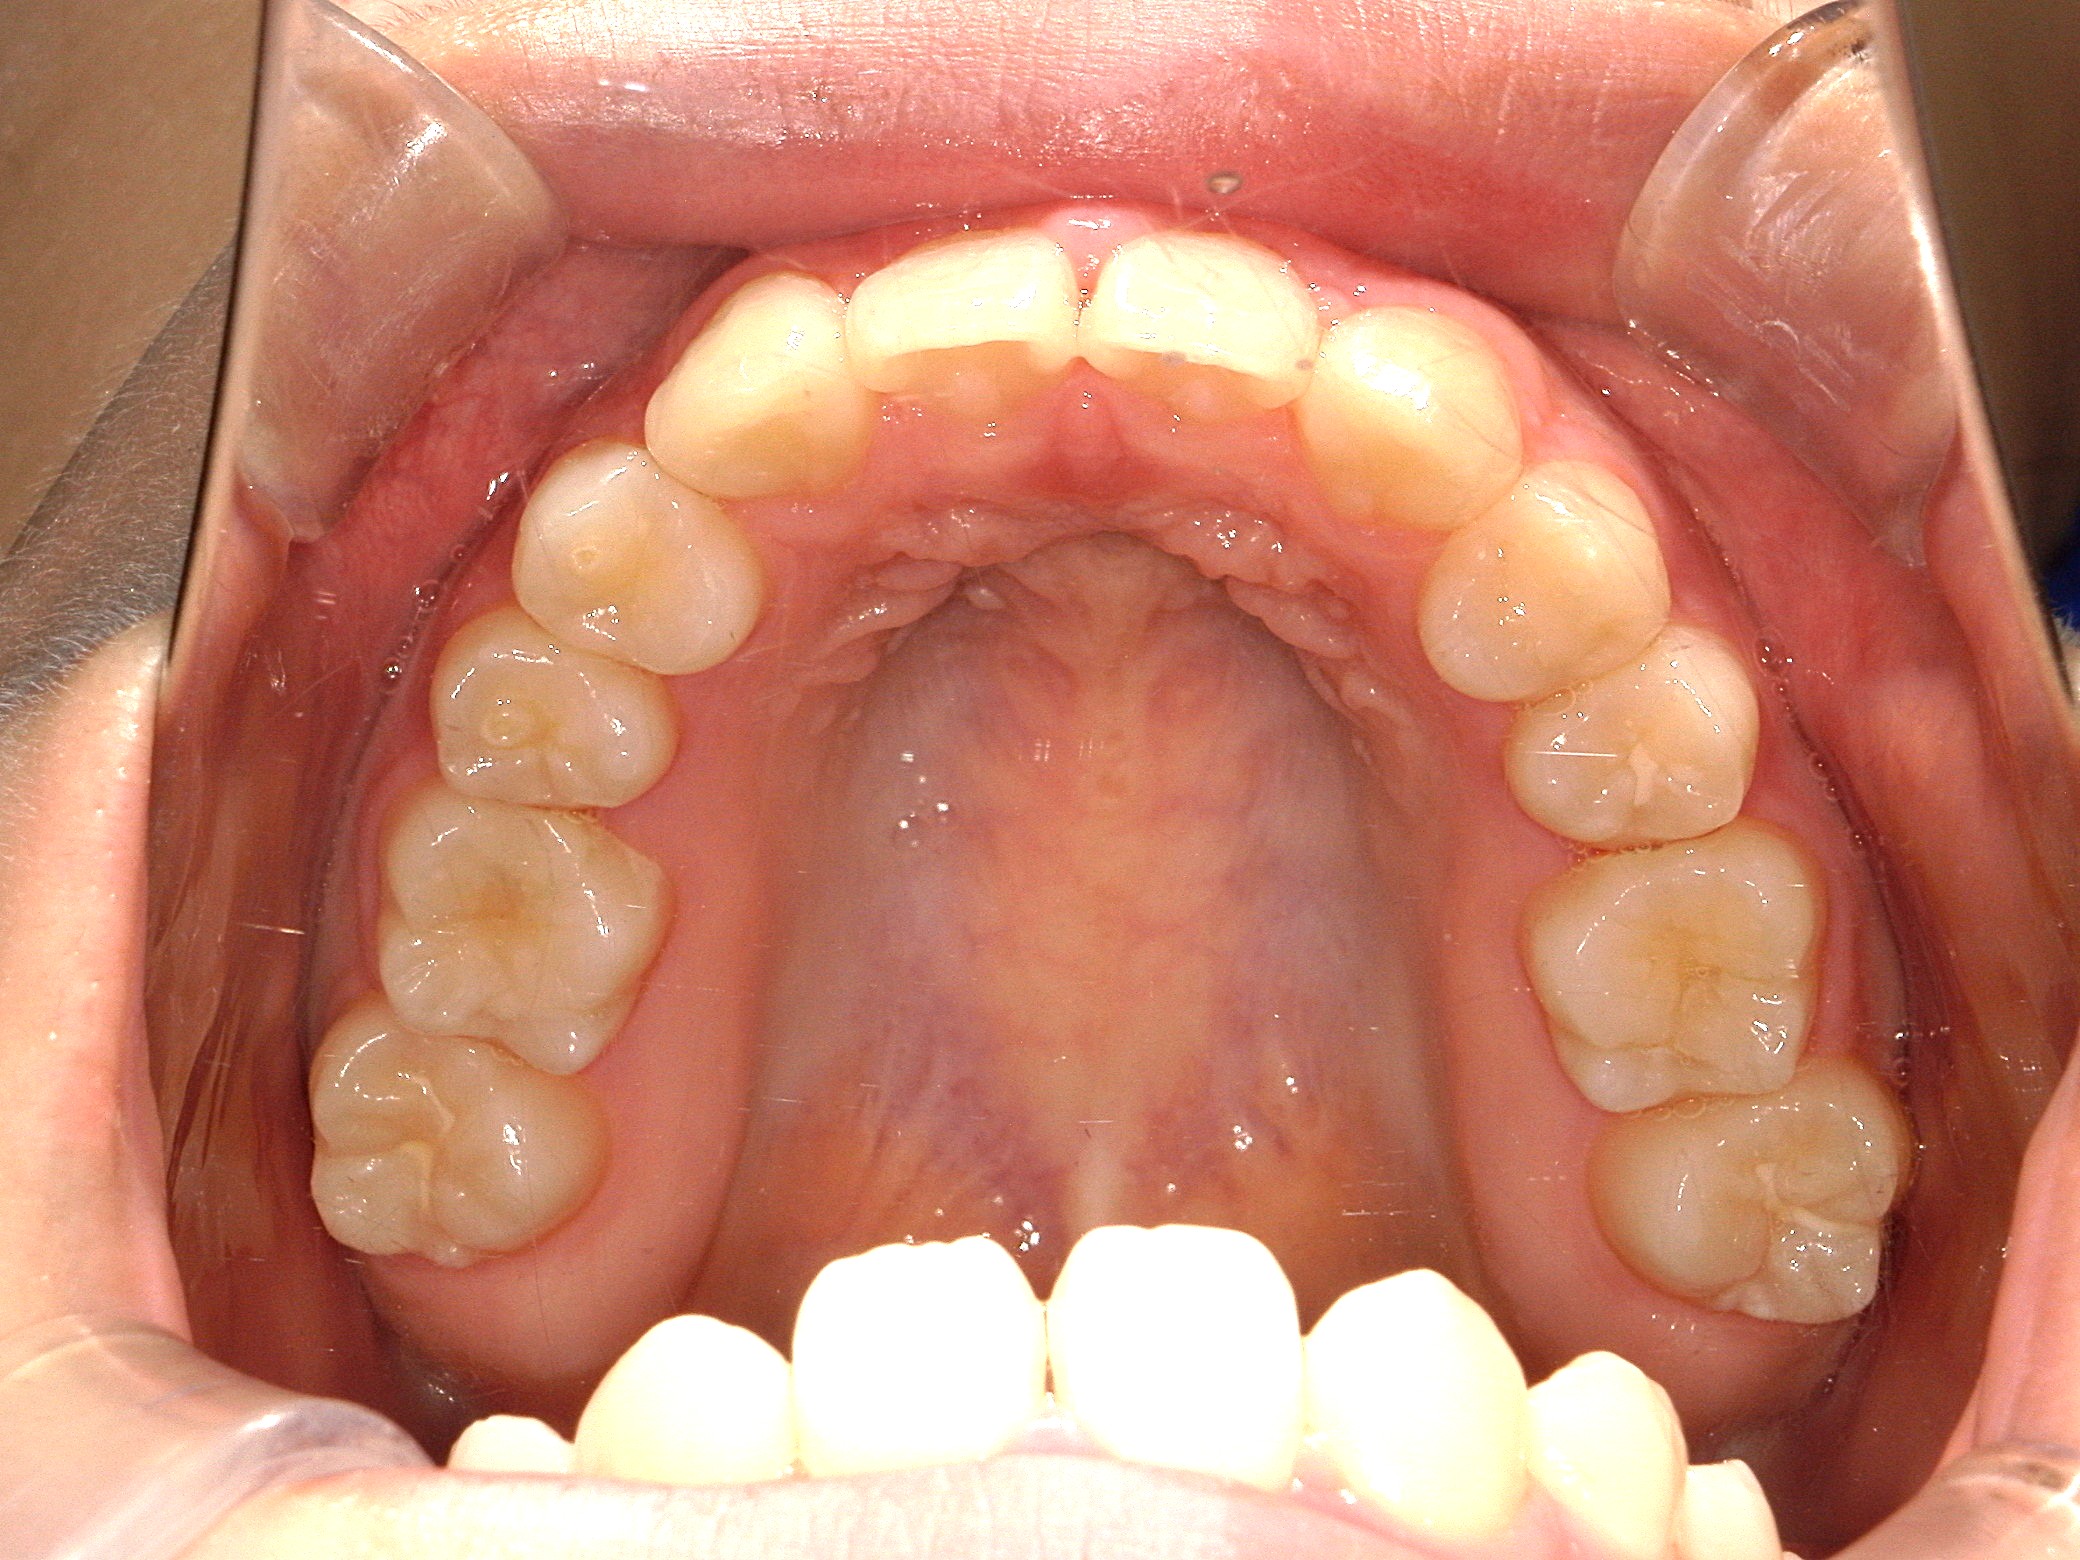

口内上

治療後

歯を並べる隙間を作るため、上下共に歯を抜いて治療を行うこととしました。

上は矮小歯を、下は横の歯を抜いて治療を行いました。

上の歯は2番の歯を犬歯で代替しているので、上下の大きさの違いが出るのですが、不自然にならないよう幅をわずかに調節して仕上げています。